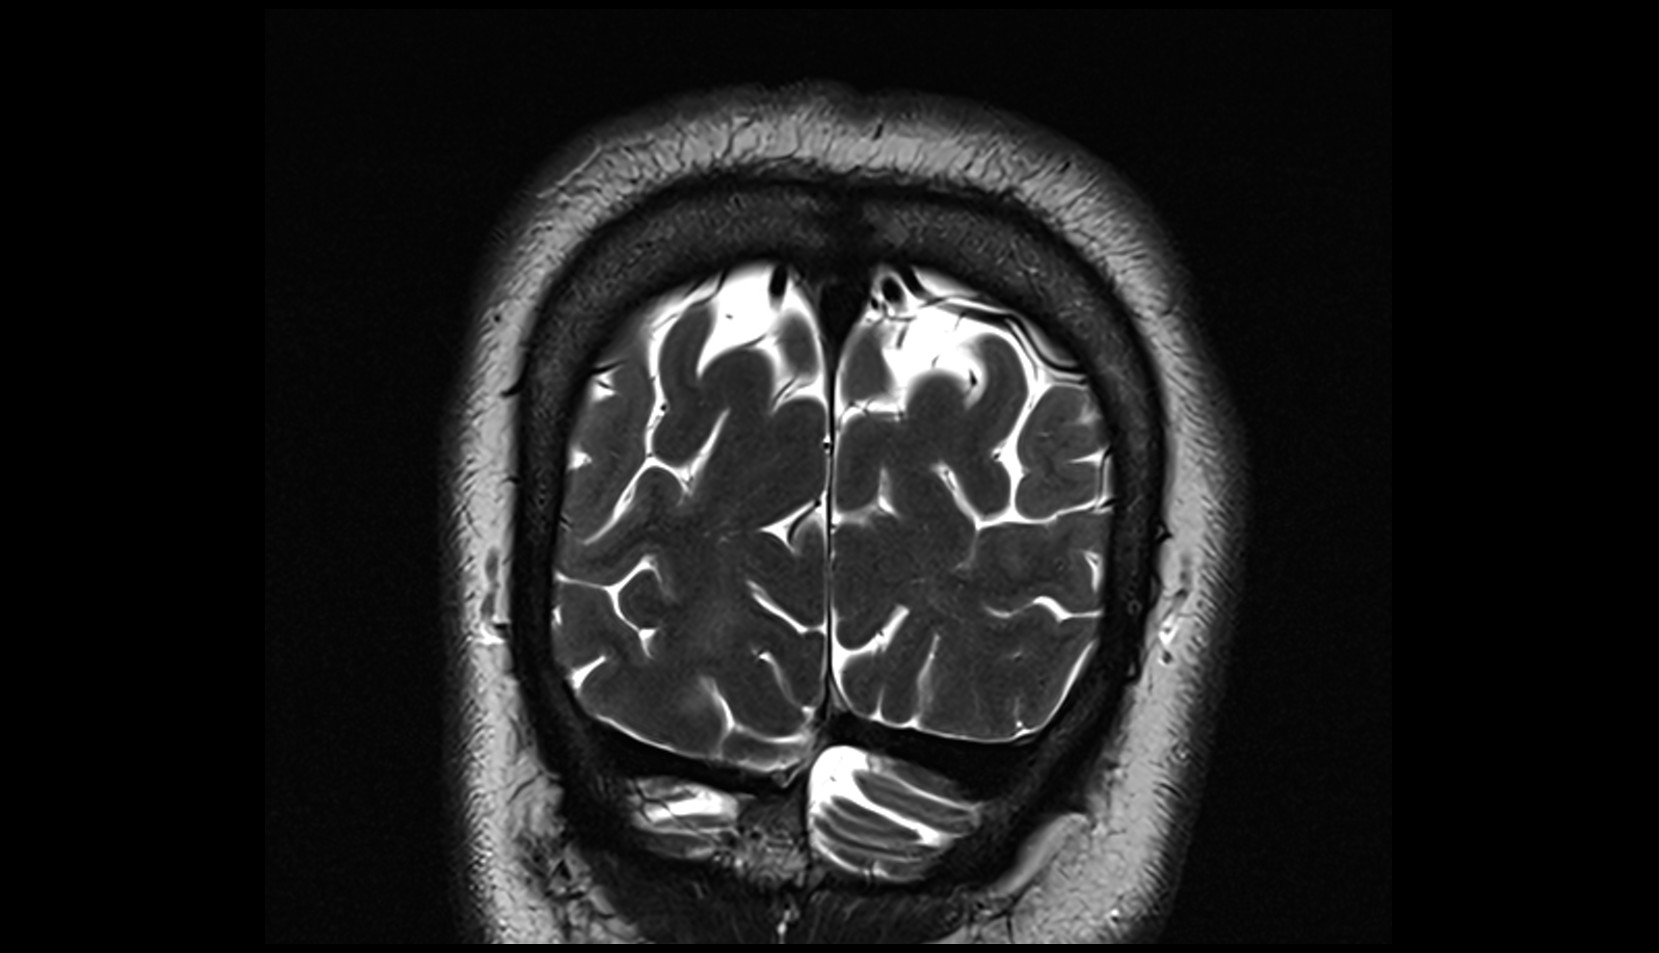

- Fetal brain

- Fetal cerebellum

- Fetal frontal lobe